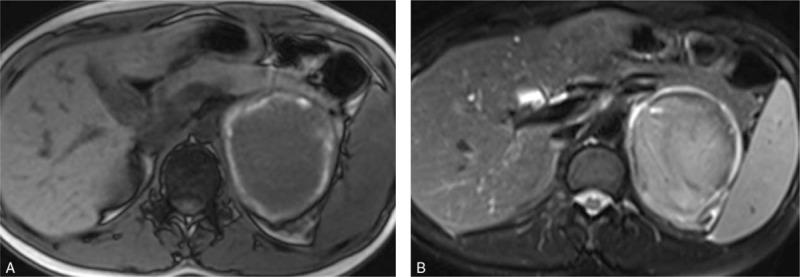

MR scan of the abdomen revealed an 8.1 × 7.7 × 6.8 cm round mass in the left adrenal region, which showed a rim of acute hemorrhage signal. Due to the stable condition of the patient and fetus, she was admitted for observation. Repeat MR scan was performed a month later, and it showed a stable mass with marginal subacute bleeding signal.

The most important characteristic of adrenal hematoma is the high-signal rim on T1-weighted MR images, and the clinicians should make individualized treatment plan for every patient encountered in the future who might have different clinical conditions.

腹部磁共振扫描显示左肾上腺区有一8.1×7.7×6.8厘米的圆形肿块,周边有急性出血信号。鉴于患者及胎儿情况稳定,收住入院观察。一个月后复查磁共振扫描,显示肿块稳定,周边有亚急性出血信号。

肾上腺血肿最重要的特征是在T1加权磁共振图像上有高信号边缘,临床医生应对未来遇到的可能有不同临床情况的每位患者制定个体化治疗方案。